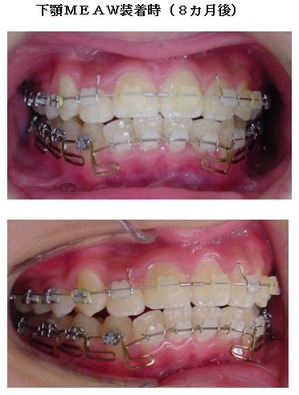

当院ではマルチループ(MEAW法)という上の写真で装着しているようなクネクネ曲がったワイヤーを使用して、上下の隙間を埋めていくことで歯並びを整えます。

次にMEAW(マルチループ)を利用する事で咬み合わせの高さや前歯の傾斜を整えていきます。

また、MEAW(マルチループ)はゴムを24時間使用する事で最大の効果を発揮することが出来ます。

当院では簡易なMEAW(マルチループ)を使用する事で上下の前歯部をより綺麗な歯並びにしていきます。

この時にも24時間使用するゴムが大切です。